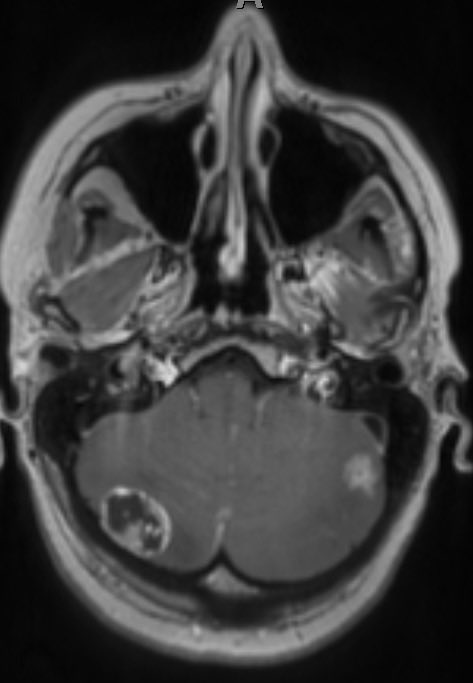

Fundraisers take on huge cycling challenge for Burgess Hill woman with ten brain tumours | SussexWorld - 🙌🏻 to everyone involved with WellerFest raising vital funds for Brain Tumour Research & UKALK+ 💛 sussexexpress.co.uk/health/fundrai…